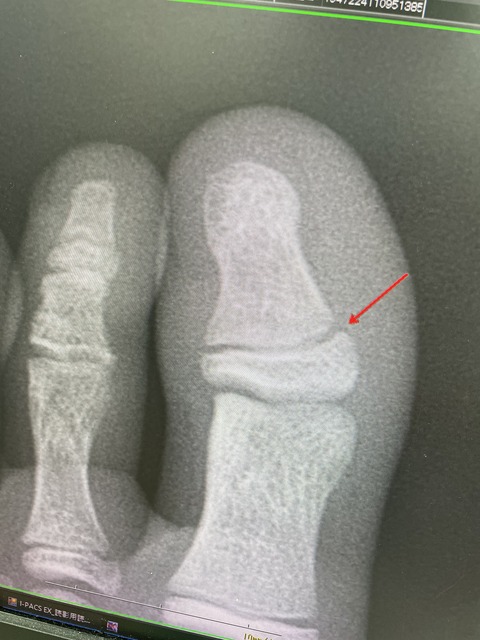

練習中に足の怪我をしました、